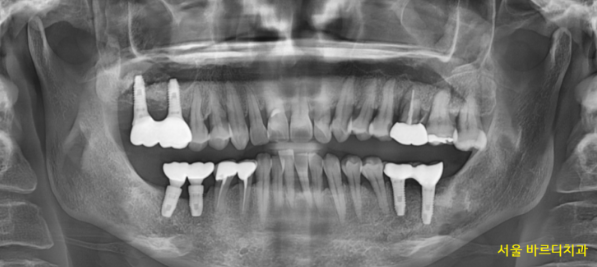

230610

3월에 염증을 긁어내고

1차 뼈이식을 진행

3개월 정도 지나 뼈가 어느 정도 찼을 때

2차 뼈이식과 미사역 임플란트를 진행하였습니다.

2차 뼈이식을 진행하면서

상악동도 들어올리는 부가적인 수술을 같이했습니다.

231120

미사역 임플란트 식립 후 5개월이 지나

보철을 완성한 사진입니다.

발치 후 3개월

뼈이식 후 5개월

8개월이 지나 진료가 끝났습니다.